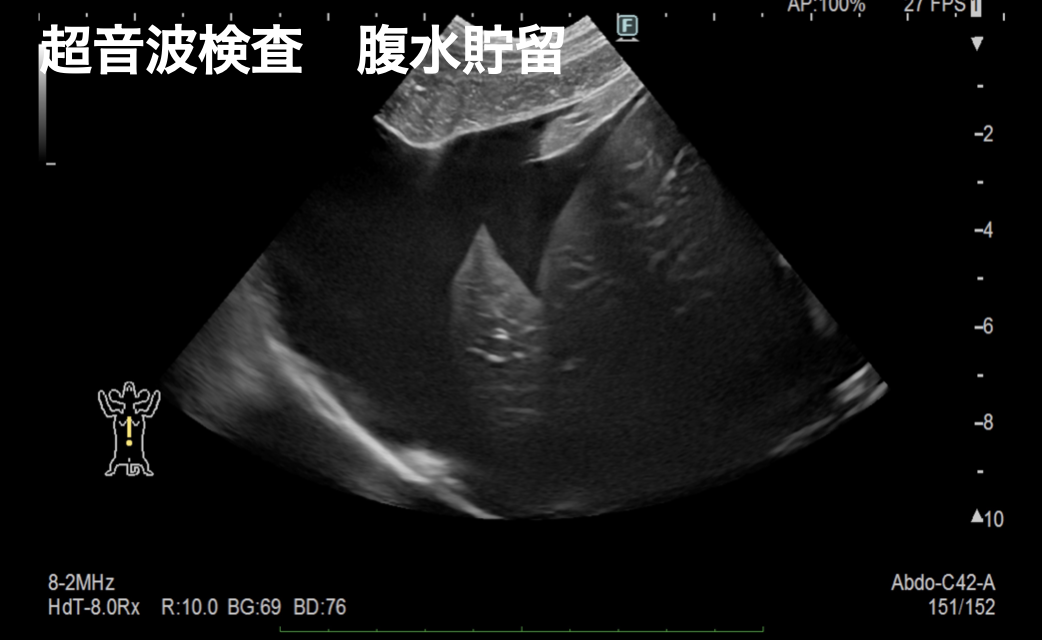

食欲不振、元気消失、嘔吐を主訴に動物病院を受診し、腹水貯留の精査のためCT撮影、導尿処置によって尿道閉塞による膀胱破裂と診断されました。